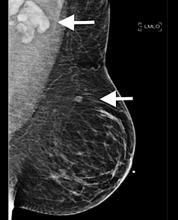

December 7, 2021 — According to an open-access article in ARRS’ American Journal of Roentgenology (AJR), screening disparities that were exacerbated by the coronavirus disease (COVID-19) pandemic can be mitigated by strategies to increase access, targeting facilities serving vulnerable patient populations.

Single vs. Multiple Architectural Distortion on Digital Breast Tomosynthesis

Digital Breast Tomosynthesis Spot Compression Clarifies Ambiguous Findings